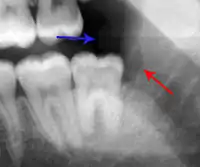

Decay (green) with apical abscess (blue)

Gutta-percha point indicating abscess origin